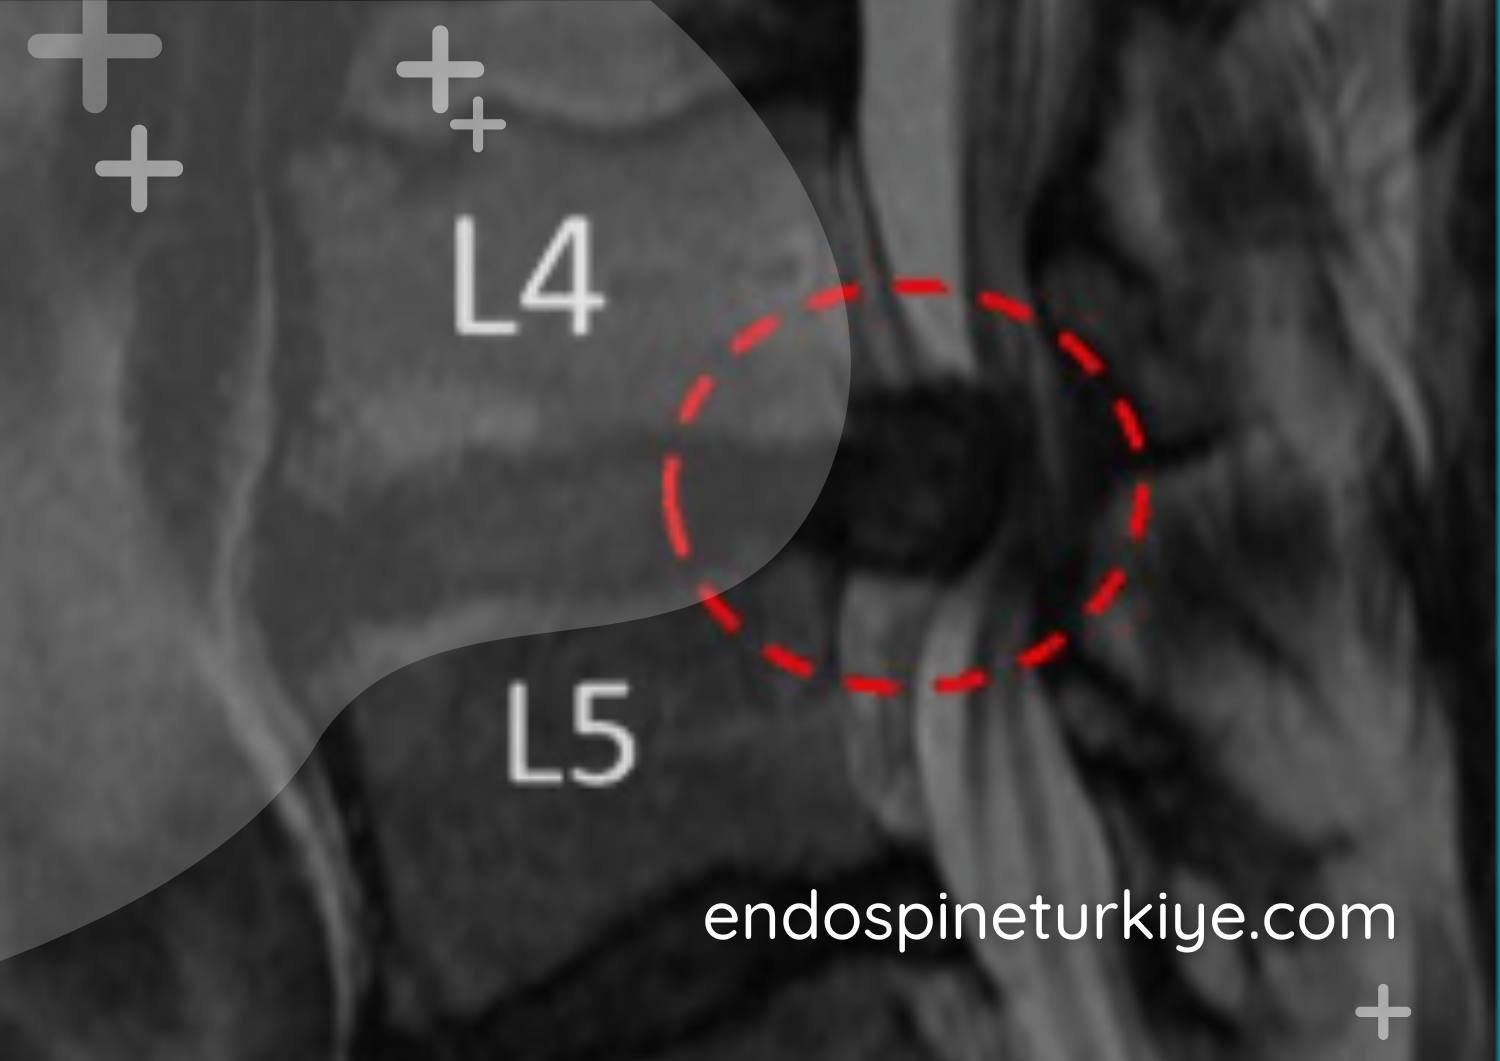

Tam kapalı dar kanal ameliyatı öncesi lomber MR - kanal darlığı teşhisi

Lomber MR görüntüsü - omurga kanalında daralma (spinal stenoz)